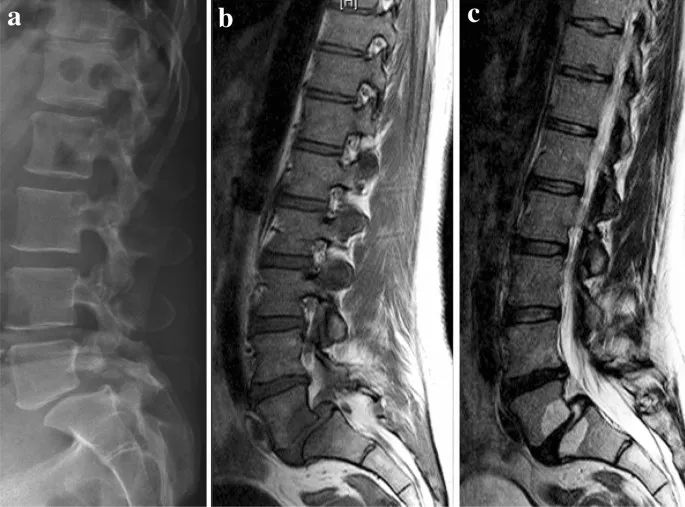

△ 老化脊柱的影像(图片来源:SpringerLink)

脊柱退行性病变

脊柱退行性变是老年人中非常普遍的脊椎疾病,主要包括椎间盘退变、椎体骨质增生(骨刺)和脊柱关节炎等。随着年龄的增长,脊柱的各个结构如椎间盘、韧带和关节会逐渐发生退行性变化,导致脊柱稳定性和柔韧性下降,并可能引起疼痛、麻木、无力等症状。

研究表明,80%的人群一生中会经历不同程度的颈腰背痛。